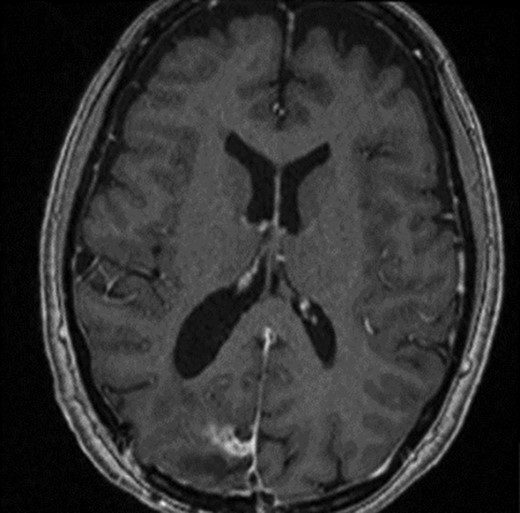

A 52-year-old female presented with headache and visual disturbance. She had no significant past medical history. On examination, a left homonomous inferior quadrantopia was noted. CT and then MRI imaging revealed a solitary 3-cm right parieto-occipital extra-axial lesion with associated dural tail and surrounding oedema (Fig. 1). Her headaches improved with a short course of steroids and the neuro-oncology MDT recommendation was for surgical excision of the suspected meningioma.

Axial view of a T1 weighted MRI post-gadolinium enhancement demonstrating the appearance of a 3-cm right parieto-occipital extra-axial mass with bony involvement and adjacent small nodule. Most in keeping with a meningioma.